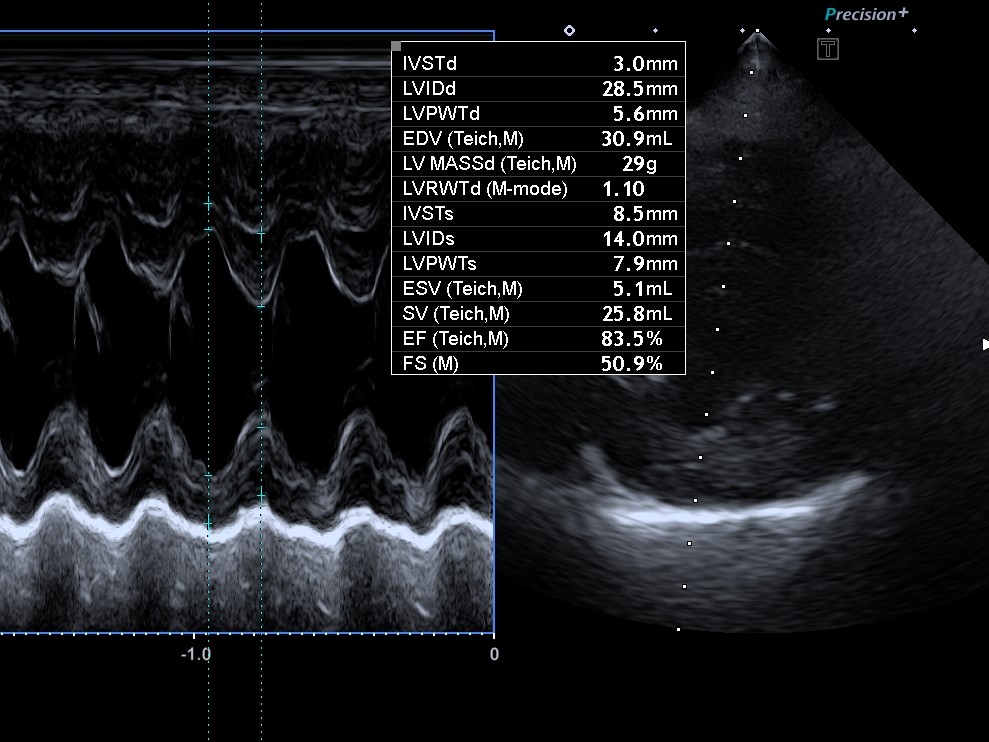

- 심장 초음파 검사: 심장의 구조적 변화 확인 (심실 확장, 승모판 이상 등)

특히 초음파 검사 결과에서 좌심방 크기(Left Atrium Enlargement) 가 커졌다면,

이는 이미 병이 상당 부분 진행됐다는 신호일 수 있다.